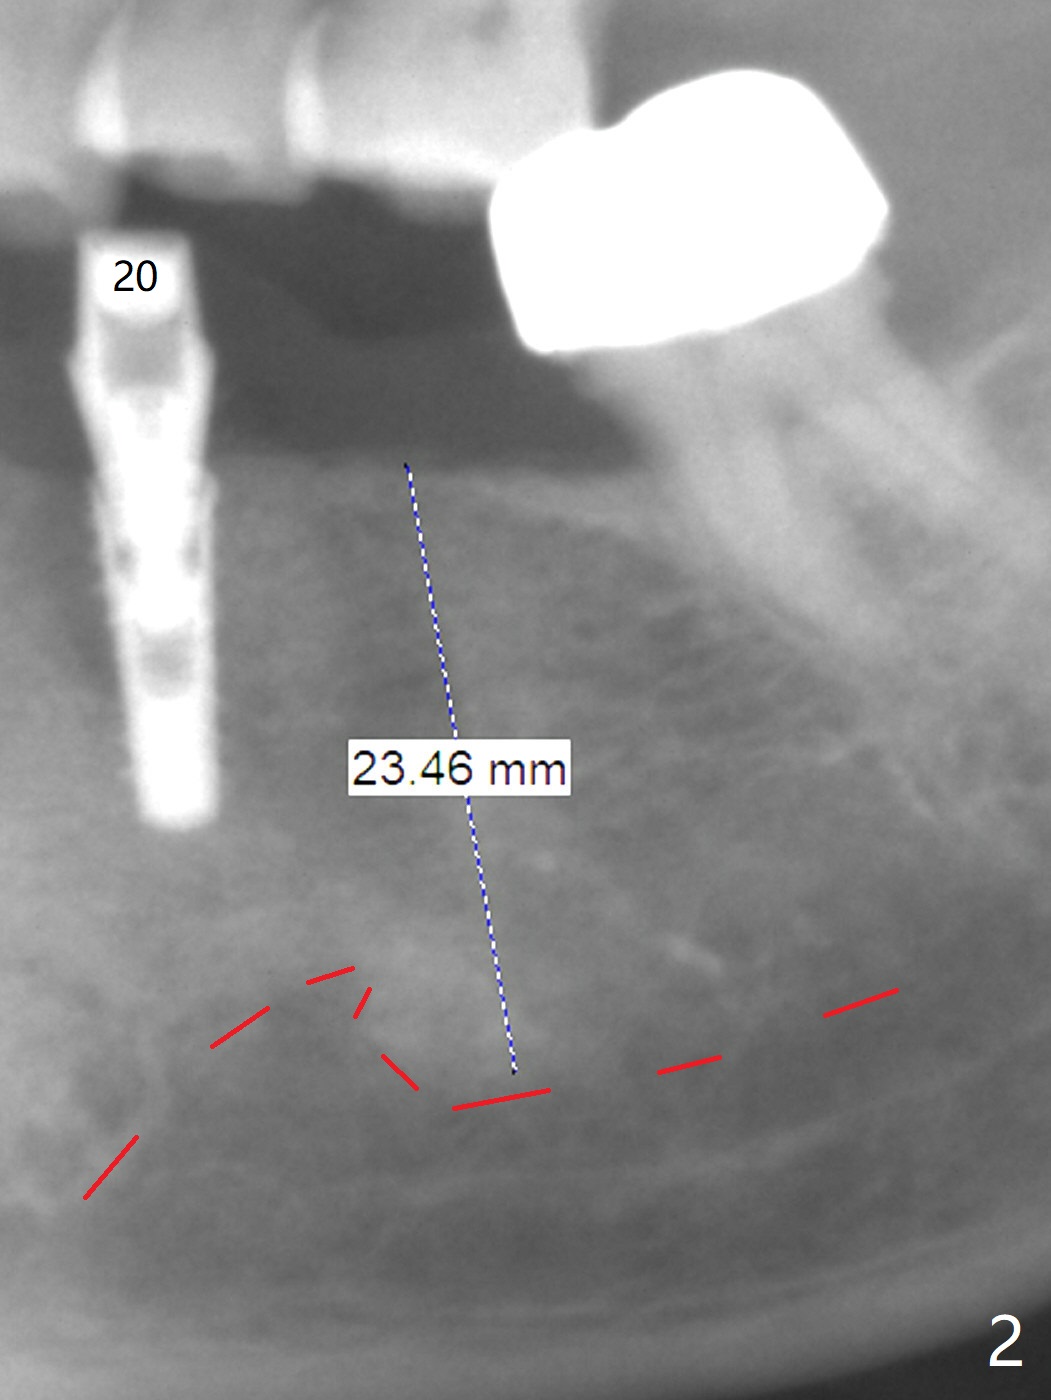

A 65-year-old woman will return for implant placement at #19 pontic area (Fig.1) nearly 3 months post implant placement at #20 (Fig.2). Since the edentulism should be long standing, the ridge must be narrow buccolingually. On the other hand, the ridge is long coronoapically (Fig.2). Ridge reduction will be conducted. If the width can be gained for 5 mm with less than 3 mm height reduction, a 4x7(3) mm Magicore will be placed. Otherwise a long 1-piece implant is to be chosen. The narrow implant (3 or 4 mm) is justifiable because of relatively small mesiodistal space at the pontic. Prepare implant positioners of 3 and 4 mm.